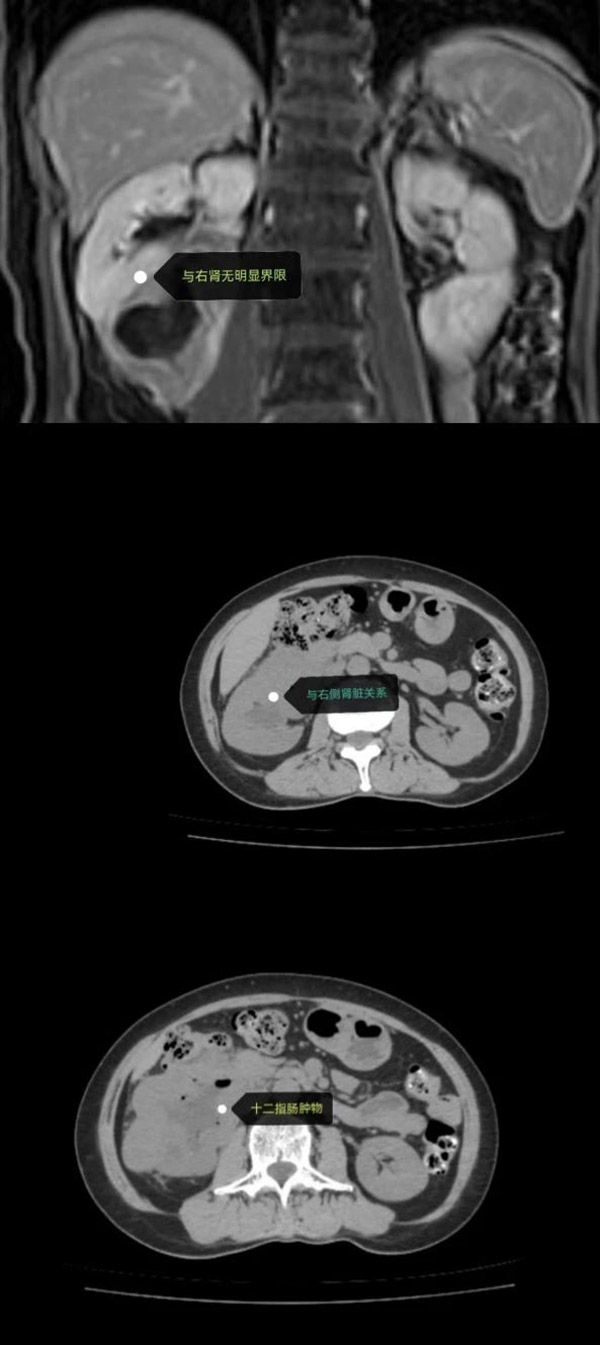

面对十二指肠来源、侵犯右肾的罕见巨大间质瘤,沈阳市第十人民医院(沈阳市胸科医院)普外科任庆华主任团队、泌尿外科李阳主任与麻醉科王涛主任团队强强联手,在肿瘤与升结肠、血管紧密缠绕的“手术禁区”中精准“拆弹”,不仅完整切除肿瘤,更成功保留患者升结肠!这场手术是多学科协作的典范,彰显了医院攻坚疑难重症的硬核实力。

肿瘤如“树根”般深扎于十二指肠、右肾及升结肠之间,稍有不慎便可能引发大出血或肠道损伤。任庆华主任团队凭借丰富经验,在复杂血管网中剥离肿瘤;李阳主任精细处理受侵肾脏组织,最大限度保留功能;麻醉科王涛团队全程护航,稳控生命体征。三学科无缝配合,最终在完整切除肿瘤的同时,奇迹般保住升结肠!

“这不是单打独斗,而是团队作战的胜利!”专家团队采用术前3D影像精准规划、术中多学科实时决策、术后快速康复管理,将“保器官、降损伤”理念贯穿全程。手术不仅避免了二次肠造瘘,更缩短患者康复周期,标志着医院在复杂肿瘤综合治疗领域实现新突破。